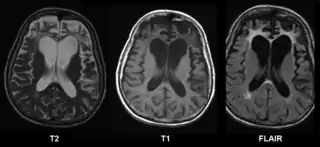

Se encuentra disponible una serie de pruebas neuropsicológicas para esclarecer la naturaleza y la extensión de la disfunción del lóbulo frontal. Por ejemplo, la formación de conceptos y la capacidad para cambiar la disposición mental, se podría medir con la Prueba de Ordenamiento de Tarjetas de Wisconsin, y la planificación se evaluaría con la subprueba de Laberintos del WISC.[3] La demencia frontotemporal aparece como una atrofia de la corteza frontal en la RMN.[20] En las pruebas de diagnóstico por imagen también se mostrará el deterioro de la región frontal causado por traumatismos craneoencefálicos, tumores o enfermedades cerebrovasculares.[4]